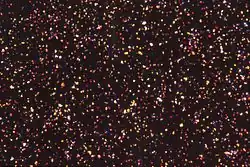

Plasmodium falciparum hemozoin crystals under polarised light.